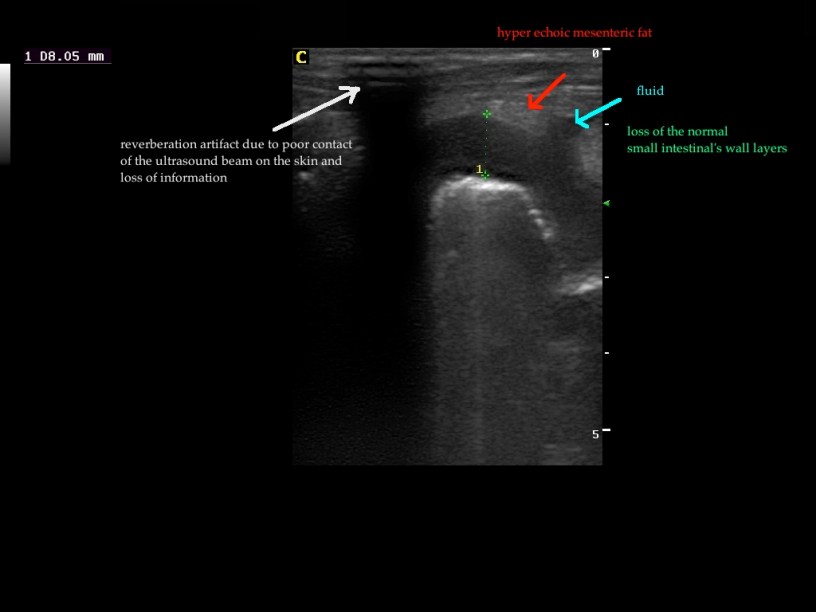

Findings: The ultrasound exam revealed a marked distention of a segment of the small intestine which ended in a narrowed lumen due to a thickened wall. The mesenteric lymph nodes were markendly enlarged and hypoechoic. A fine needle aspirate was performed.

The GIF shows the frames from the normal small intestinal layering to the thickened abnormal wall in a perpendicular view.